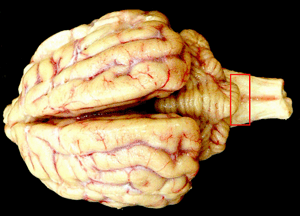

| 赤線で囲まれた部分にプリオンが溜まる |